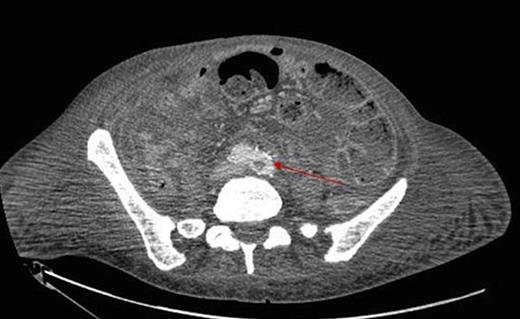

During inpatient stay, she became haemodynamically unstable with spiking temperatures and an elevating white cell count. She also complained of bilateral discolouration of her toes and examination revealed increasing oedema with diminished pedal pulses. A contrast CT scan of the abdomen confirmed ongoing collections with evidence of an aortic thrombus extending into the left iliac artery, presumed to be the embolic source for her vascular findings (figure 2 & 3). She underwent a further laparotomy and washout, and was heparinised postoperatively. There was resolution of vascular symptoms and evidence of improvement in peripheral perfusion postoperatively, and the patient was eventually discharged.

Extension into the left iliac artery shown by a filling defect (red arrow)